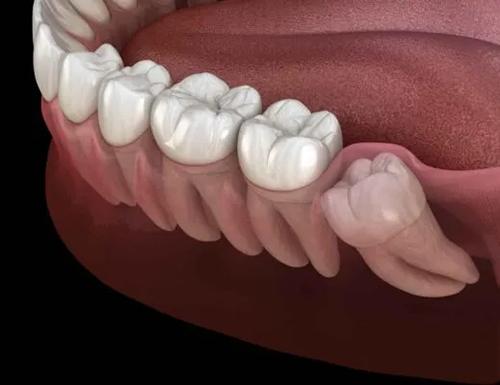

사랑니는 언제 뽑아야 할까?

안녕하세요 목동안치과의 안상우 원장입니다.오늘은 사랑니에 대한 이야기를 한번해보고자 합니다.사랑니에 대해서는 한번쯤은 들어보신적이 있으실꺼에요.사랑니는 치아의 제일 뒤에 있는 치아로 제3대구치라고도 합니다. 막니라고도 해요.맨 뒤에 있기 때문에 인지를 못하는 경우도 있고 맨 뒤에 있기 때문에 관리하기가 쉽지 않습니다. 또한 잇몸 밖으로 나오지 않는경우도 있습니다.사랑니는 우리몸의 진화과정과 관련이 있습니다.먼 옛날 우리의 선조들의 음식들은 대부분 질긴경우가 많았어요.조리가 되지 않았거나 잘 다듬어지지 않은 음식 들이었겠죠질긴음식을 먹기 위해서는 턱이 커야 했고 치아가 많아야 했어요.그래서 사랑니가 정상적인 대구치처럼 사용되고 있었습니다.하지만 현대에 들어서 음식이 부드러워지고 섭취하기 쉬워지면서 현대인들은 원시의 선조들보다 턱의 크기가 작아지게 되었습니다.그러다보니 자연스럽게 맨 뒤에 있는 치아는 있을 자리가 없어지면서 비정상적인 형태로 나오기 시작했습니다.사랑니는 어떻게 보면 퇴화하는 기관중에 하나에요.이 사랑니는 어떤 경우에는 그냥 두거나 사용할수 있고 어떤경우에는 뽑아야 하는경우도 있습니다.사랑니는 치아 중 맨뒤에 나는 치아로 칫솔질로 관리하기 힘든 위치에 있습니다.정말 관심을 가지고 관리를 하지 않는 이상 이 부위에는 이물질이 자주 저류되게 되요.사랑니가 아예 잇몸안에 들어가 있다면 외부의 이물질이 들어가거나 하지 않기 때문에 문제를 발생시키지 않습니다.하지만 사랑니가 구강내로 부분적 또는 완전히 맹출했을 경우에는 사랑니 주변에 이물질이 남아 있을수 있습니다.우선 뽑아야 하는 사랑니중에 첫번째는 일단 충치가 생겨서 통증을 유발할 때입니다.이런경우에는 관리가 잘 안되는것이기 때문에 발치를 해주는것이 좋습니다.충치가 있어도 똑바로 나와 있으면 치료를 해서 사용할수도 있기는 합니다.하지만 치아가 뒤에 있어서 치료가 다른치아보다 상대적으로 어려워서 치료에 한계가 있을 수 있습니다.두번째 경우로는 사진과 같이 사랑니가 팔자좋게 옆으로 누워있다면 발치를 해야 하는 대표적인 사랑니중에 하나에요.사랑니가 기울어져 있게 되고 잇몸에 부분적으로 맹출되어 나와 있게 되면 사랑니와 앞에 있는 치아 사이에 음식물이 자주 들어 갈수 있습니다.이런식으로 잇몸에 염증을 일으킬수 있거나 앞에 치아에 충치를 발생시킬 가능성이 있는 사랑니라면 발치 해줘야 합니다.사랑니는 위아래 같이 존재하게 되는데 한쪽의 사랑니는 똑바로 나왔는데 다른 쪽 사랑니가 나오지 않았거나 발치되었다면 맹출되어 있는 사랑니가 정출될 수 있습니다.치아가 정출되게 되면 치열이 어긋나게 되어 해당부위에 음식물이 들어 갈수 있어요.또한 반대편 잇몸을 자극하게 되어 잇몸에 상처가 나고 통증이 있을수 있습니다.이런 경우에도 발치를 해야 하는경우입니다.일단 사랑니가 똑바로 나와 있고 위아래 치아가 정상적으로 교합을 하고 있다면 발치를 하지 않아도 됩니다.사랑니가 정상적으로 물리게 된다면 저작하는 기능이 증가하게 되어 다른 치아에 가해지는 힘을 분산하게 됩니다.또한 뽑지 않아도 되는 사랑니로는 완전하게 잇몸안에 들어가 있어서 앞의 치아나 잇몸에 이물질을 저류시키지 않는 경우 입니다.잇몸안에 완전히 들어가 있고 특별한 병소가 없다면 발치를 할필요가 없어요.어떻셨나요 자신의 사랑니를 뽑아야 하는지 아닌지는 사랑니가 난 형태와 위치를 확인해보세요.사랑니가 잘 기능을 하고 주변에 문제를 일으키지 않는지에 대해서 생각을 해본다면 발치를 해야 하는것인지 아닌지 구분을 할수 있습니다.치아는 하나라도 더 있는 것이 좋습니다.따라서 사랑니를 가지고 있으신분들도 사랑니라고 너무 소홀해 해지 마시고 관심을 가지고 관리를 해주는것이 좋습니다.